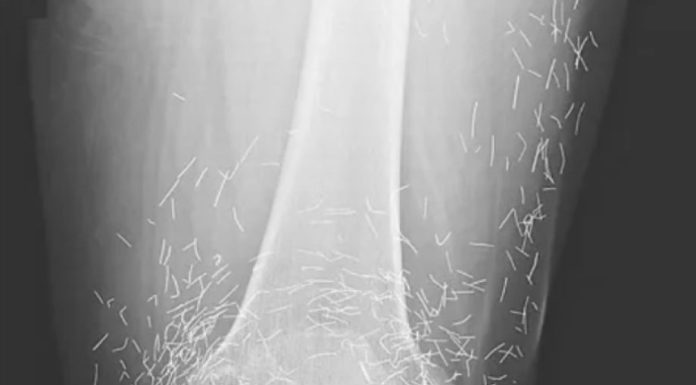

Astonishing Discovery: The Risks of Embedded Acupuncture Needles

In a remarkable twist during a routine medical examination, doctors uncovered an unexpected surprise in the knees of a 65-year-old South Korean woman. While assessing her severe joint pain, X-ray imaging revealed...